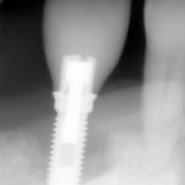

Zhao, spécialiste du massage de la tête

Crâne, cou, occipital, maxillaires, articulation temporo-mandibulaire.

Nous vous conseillons le massage Crâne, Visage et Dos : 90 minutes

Ce massage vous permettra de libérer les tensions de la malocclusion dentaire, de réduire le serrement dentaire et le bruxisme nocturne. Il réduira les céphalées, les tensions dentaires du maxillaire antérieur, et les souffrances du cou et des trapèzes.